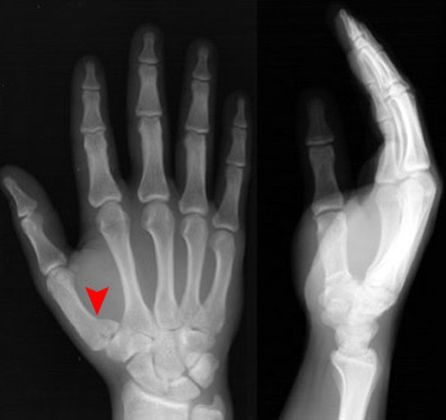

拳击手骨折

• 握拳撞击

• 通常发生在第五掌骨